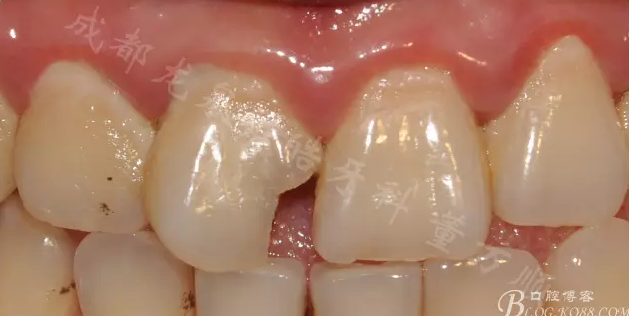

11復(fù)合樹脂充填 21鄰面樹脂充填 接觸點調(diào)磨了一部分 以保證修復(fù)體與21的比例協(xié)調(diào)

2周后復(fù)診 行瓷貼面修復(fù)